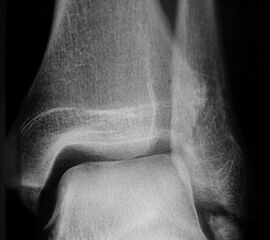

Fugengelenkfrakturen treten typischerweise vor dem 10. Lebensjahr auf, in einer Phase, in welcher die Wachstumsfugen noch weit offen sind. Dieser Frakturtyp betrifft fast ausschließlich den medialen Malleolus. Laterale Frakturen sind extrem selten, teilweise kommt es zu lateralen Bandverletzungen oder Fugenschaftfrakturen der distalen Fibula. Die Frakturlinie verläuft in einer Verlängerungslinie von der medialen Taluskante nach proximal. Häufig stellen sich Verletzungen des Innenknöchels im Röntgenbild schlechter dar, insbesondere wenn die Aufnahmen verdreht sind oder die Ebene der Fraktur bei geringer Dislokation verkippt zur Röntgenebene liegt. Besteht klinisch der geringste Hinweis auf eine Verletzung des Innenknöchels, muss aufgrund der Tragweite der Verletzung durch entsprechende Aufnahmen gegebenenfalls auch Schnittbildverfahren die Verletzung sicher diagnostiziert oder ausgeschlossen werden (Abb. 15).